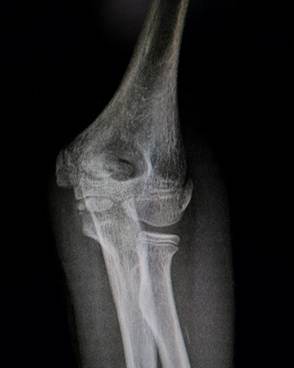

Область локтя в разном возрасте

Василий Оскарович Маркс говорил, что неподготовленный человек на

снимке локтевого сустава здорового ребенка найдёт восемь переломов. Очень даже

может быть – рентгенологическая картина локтя ребенка в возрасте от года до

четырнадцати лет насыщена ядрами окостенения и зонами роста, которые легко

принять за костный отломок или осколок, особенно если в анамнезе есть травма.

1 год - 3 года

В возрасте года выявляется булавовидный метафиз плечевой кости,

ядро окостенения головчатого возвышения и латерального вала блока.

Верхний конец лучевой кости отстоит от уровня щели локтевого сустава

достаточно далеко. Конец локтевой кости находится на уровне суставной щели. К 3

годам на снимках очерчивается основание головки лучевой кости и хорошо видна

блоковидная вырезка локтевой кости с основаниями локтевого и венечного

отростков. В самом конце периода появляется ядро окостенения головки лучевой

кости.

Прямой снимок локтевого сустава ребенка 5 месяцев. Обратите

внимание, насколько далеко отстоят друг от друга видимые,

т.е. окостеневшие части сочленяющихся костей.